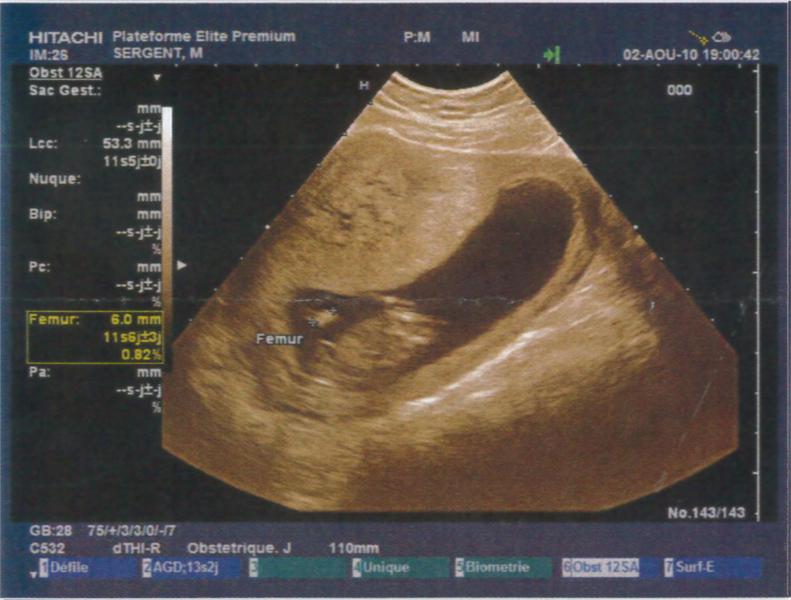

Je suis à 12SA soit 10SG, j'ai fait mon écho hier soir et tout va super bien !!! Je suis trop heureuse je vais vraiment pouvoir vivre ma grossesse à fond !! La nuque est parfaite, à vérifier par le test de la trisomie la semaine pro en même temps que la déclaration !!

Je vous met les photos des échos mais je trouve que l'on ne voit rien par rapport aux superbes images que nous avons vues !! Mais c'est pas grave, on a un super souvenir quand même !!

Pièces jointes

• echo1.jpg

echo1.jpg

53.6 KB · Affichages: 70

• echo2.jpg

echo2.jpg

53.8 KB · Affichages: 68

• echo3.jpg

echo3.jpg

52.7 KB · Affichages: 69

• echo4.jpg

echo4.jpg

55.4 KB · Affichages: 70

• echo5.jpg

echo5.jpg

50.7 KB · Affichages: 71